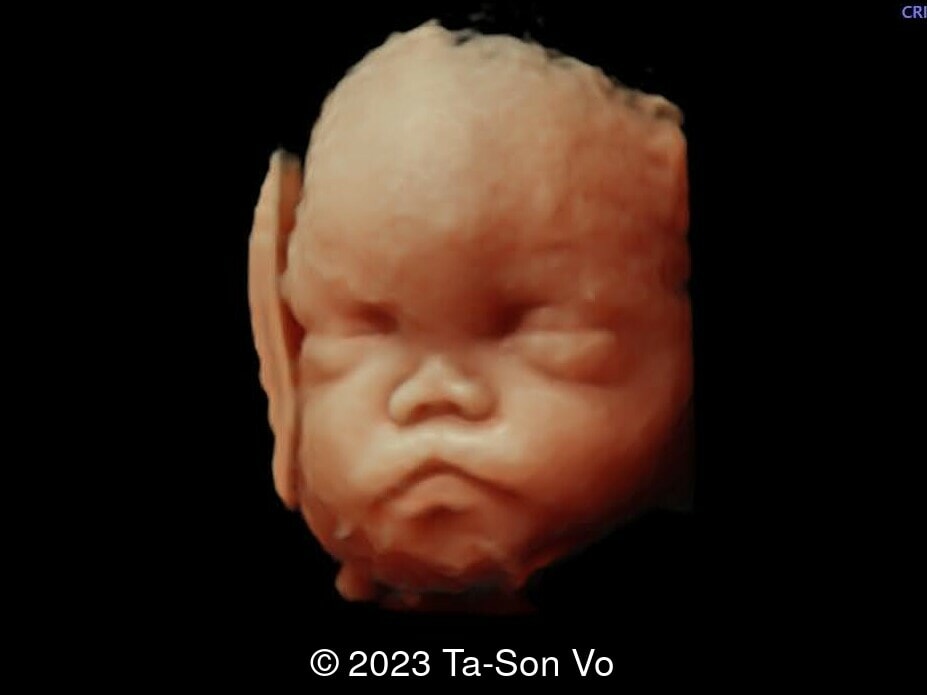

Level 2 ultrasound at 23 weeks and 28 weeks of gestation revealed thick nuchal and prenasal skin (Image 1), frontal bossing (Image 1,2), facial dysmorphism with a short nose, anteverted nostrils, flat nasal bridge, and long philtrum (Image 3,4), hypertelorism (Image 5), mega cisterna magna (Image 6) and polyhydramnios (Image 7). There was neither congenital diaphragmatic hernia nor cardiac defects with only mild tricuspid regurgitation (Image 8). Fetal biometry demonstrates a large head with rhizomelic limb shortening (Image 9).